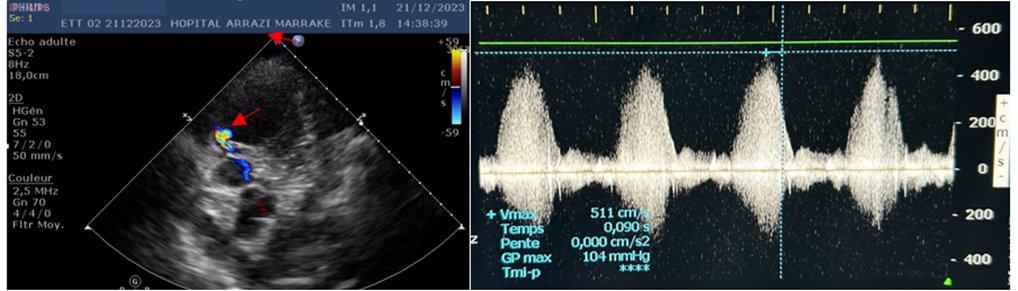

Figure 5: This 77-year-old patient was admitted with post-MI angina in inferior position, extended to the right shunts at H24, complicated by cardiogenic PAO. Echocardiography showed acute mitral insufficiency, on segmental hypokinetic cardiopathy with severe 30-35% LV dysfunction.